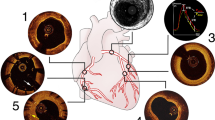

The OCT imaging revealed several plaque features not visible with other imaging modalities, e.g. Doppler ultrasound, computed tomography (CT) angiography, contrast enhanced magnetic resonance (MR) angiography, and cerebral angiography done before CAS. In all patients, normal vessel wall architecture beyond the plaque was visible, with all three layers and internal/external lamina apparent (Fig. 2a). Of the patients one had evidence of free intraluminal red thrombus with signal attenuation beyond the thrombus (Fig. 2b) and irregular thin fibrous cap dissection (Fig. 2c). Other patients had evidence of thin cap fibroatheroma and ulcerative plaque below (Figs. 3c and 4c).

Optical coherence tomography (OCT) images of a 45-year-old man. a Atherosclerotic changes beginning in cervical internal carotid artery (ICA) with areas of thick fibrous plaque (yellow arrowhead) present along with normal vessel wall architecture (red arrowhead) with visible internal/externa lamina. b Intraluminal red thrombus (yellow arrowhead) with signal attenuation beyond the thrombus (green arrowhead). c–d Irregular fibrous plaque with dissection causing luminal narrowing (yellow arrowheads). Asterisk denotes the shadow from the guidewire

Angiographic and optical coherence tomography (OCT) images from a 61-year-old man. a Cerebral angiogram showing moderate stenosis (black arrowhead). b Post-stenting angiogram showing luminal expansion. c OCT image showing a thin fibrous cap (yellow arrowhead) over an ulcerative plaque core. d Post-stenting OCT imaging showing satisfactory stent-wall apposition (green arrowhead) and plaque protrusion/thrombus through the stent struts in two locations (yellow arrowheads). Asterisk denotes the shadow from the guidewire

Angiographic and optical coherence tomography (OCT) images from a 71-year-old man. a Cerebral angiogram showing proximal common carotid artery (CCA) irregular stenosis (black arrow). b Post-stenting angiogram showing luminal expansion. c OCT image showing a very irregular plaque (yellow arrowheads). d Post-stenting OCT imaging showing satisfactory stent-wall apposition (yellow arrowhead) and collapse of the irregular plaque, with no evidence of protrusion. Asterisk denotes the shadow from the guidewire

The use of OCT was able to characterize stent/vessel wall and stent/plaque interactions clearly. For one patient, plaque herniation through the stent was demonstrated along with thrombus (Fig. 3d). Another patient had poor stent apposition as visible on OCT and underwent subsequent balloon angioplasty. All other patients had satisfactory stent apposition (Fig. 4d).